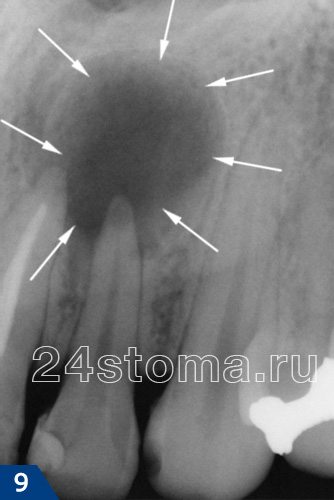

На рентгенограмме: в области верхушки корня зуба определяется затемнение с четкими ровными контурами округлой формы. Это затемнение говорит о том, что в этом участке рассосалась костная ткань. Ровные четкие контуры такого затемнения говорят о том, что образование (кистогранулема или киста) имеет плотную капсулу, не связанную с окружающей костной тканью.

На рентгенограмме: в области верхушки корня зуба определяется затемнение с четкими ровными контурами округлой формы. Это затемнение говорит о том, что в этом участке рассосалась костная ткань. Ровные четкие контуры такого затемнения говорят о том, что образование (кистогранулема или киста) имеет плотную капсулу, не связанную с окружающей костной тканью.

Хронический гранулематозный периодонтит

Кистогранулёма.